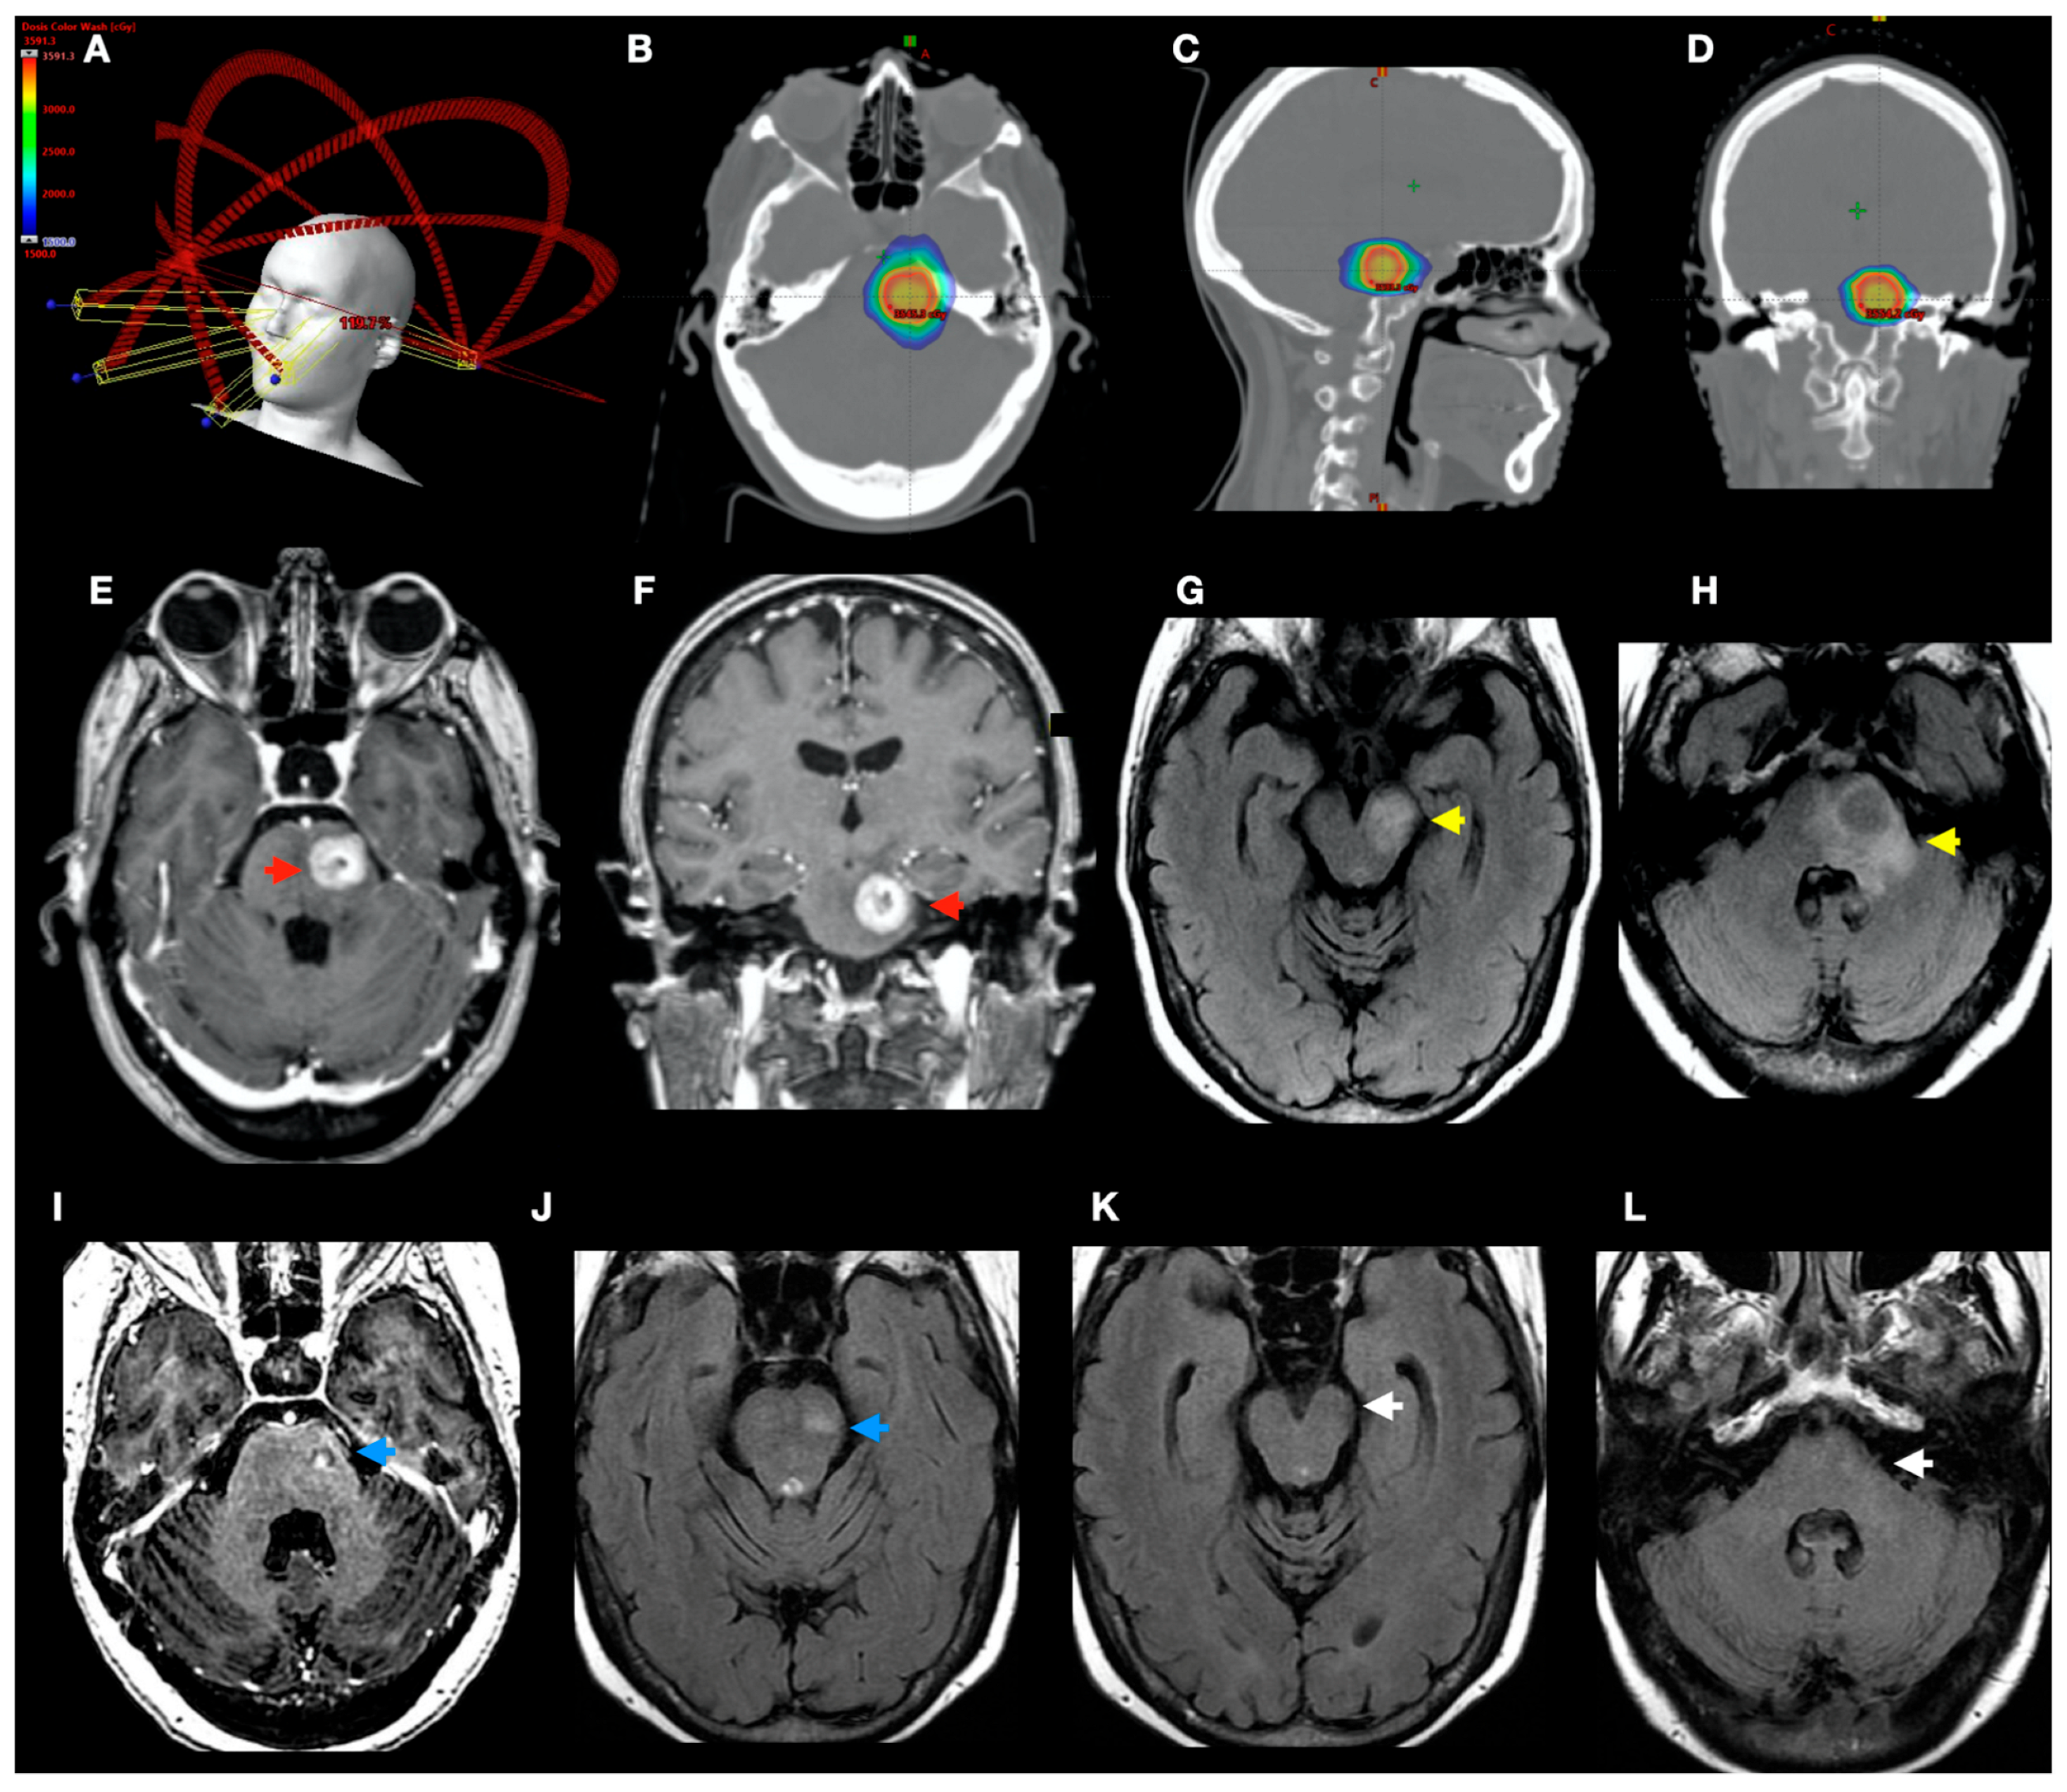

2.3. Treatment Technique

3.3. Radiological Complications of SRS Treatment